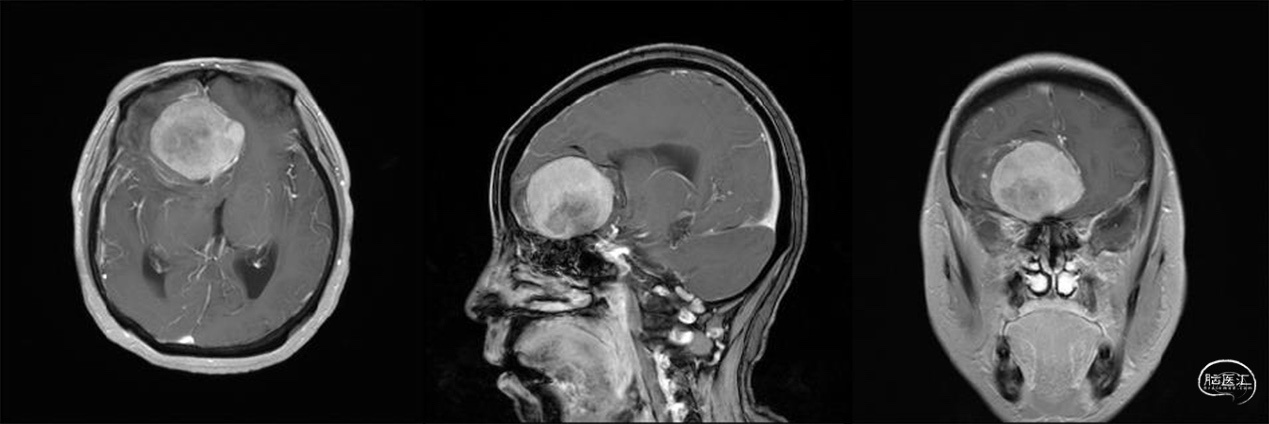

作者:董会晓

病例基本资料:

58岁,女性;

头晕10天,检查发现颅内占位;

无内科慢性病史及外伤手术病史;

神经系统查体无明显阳性体征。